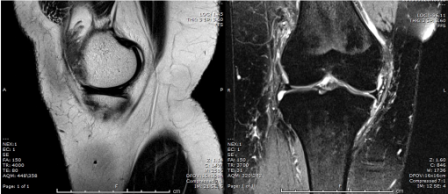

MRI is the best approach showing the masslike synovial proliferation with lobulated margins, with low signal intensity and "blooming" artifact on gradient echo due to haemosiderin deposition [4].